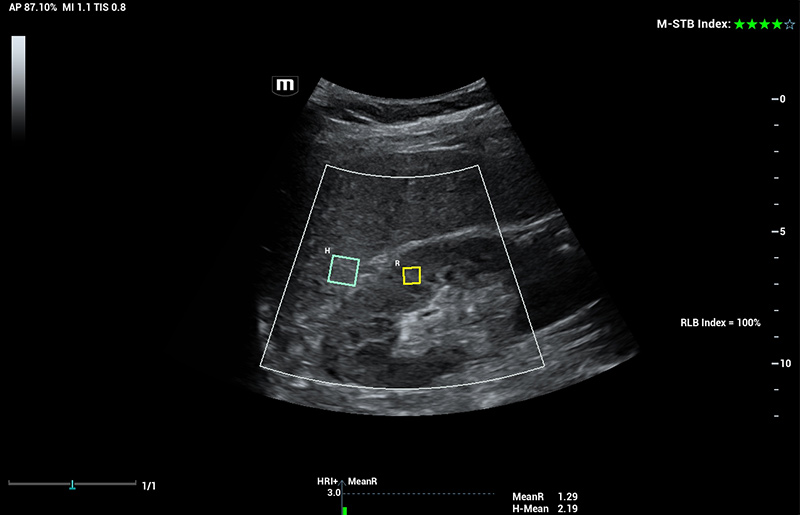

Für die Ultraschalltechnologie stellt die ZST+-Plattform einen bedeutenden Fortschritt dar, da sie statt der herkömmlichen Strahlformung die Kanaldatenverarbeitung verwendet. Diese bahnbrechende Innovation löst übliche Zielkonflikte zwischen räumlicher Auflösung, zeitlicher Auflösung und Homogenität des Gewebes auf, woraus sich eine beispiellose Bildqualität ergibt, die den Weg frei macht für unendlich viele Bildgebungslösungen.

Das Resona I9 weist umfassende klinische Lösungen für spezielle Anwendungen auf. Auf der Grundlage gründlicher Analysen verschiedener klinischer Szenarien liefert es Innovationen, die den Benutzenden herausragende Klarheit, außergewöhnliche Intelligenz und eine erhöhte Diagnosesicherheit bieten.